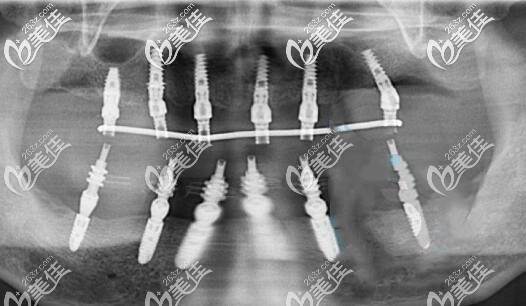

種植后拍的CT片▼